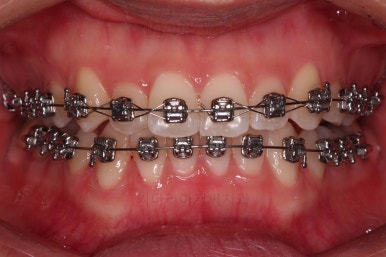

이번에 사용한 장치는 엠파워 메탈이라고 하는 자가결찰 금속 장치에요.

메탈이라고 모두 옛날방식의 장치가 아니랍니다.

"자가결찰"이냐 아니냐가 예전 장치와 요증 장치를 구분 짓는 기준이에요.

자가결찰이 아닌 세라믹이 자가결찰인 메탈보다 구세대 장치라는 거죠.

자가결찰이 여러모로 장점이 많고요.

다만, 재료에 따라 메탈도 있고 세라믹도 있어서 시각적인 차이가 있는거죠.

점점 가지런해지고 있네요.

치료가 1년만에 종료가 되었네요.

치아가 가지런해졌고, 교합이 잘 맞는 모습이에요.